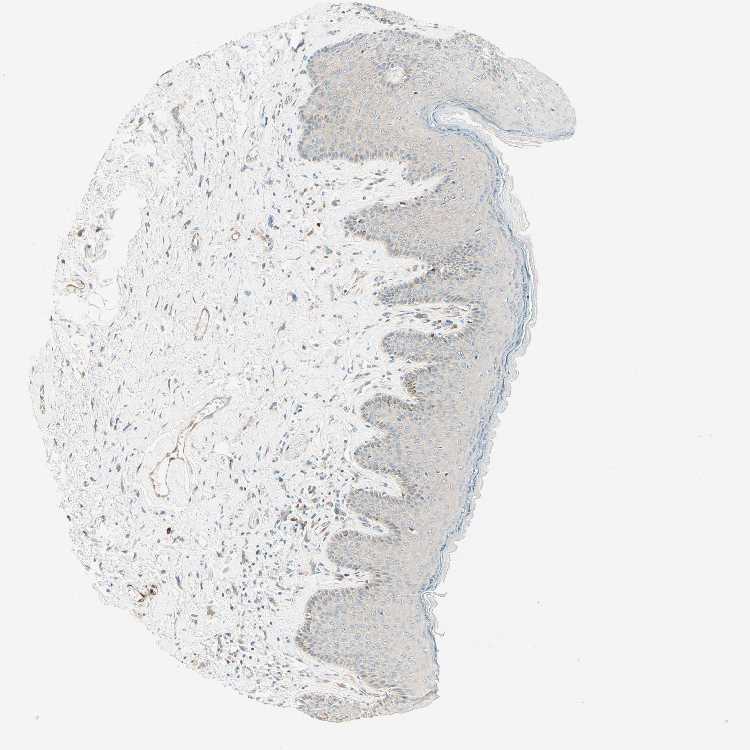

SKIN 1 - Antibody stainingi

Antibody staining in the annotated cell types in the current human tissue is reported as not detected, low, medium, or high, based on conventional immunohistochemistry profiling in selected tissues. This score is based on the combination of the staining intensity and fraction of stained cells.

Each image is clickable and will lead to virtual microscopy that enables deeper exploration of all samples and also displays staining intensity scores, fraction scores and subcellular localization as well as patient and tissue information for each sample.

Antibody HPA010650

Langerhans Low

Fibroblasts Not detected

Keratinocytes Low

Melanocytes Low

SKIN 2 - Antibody stainingi

Epidermal cells Low